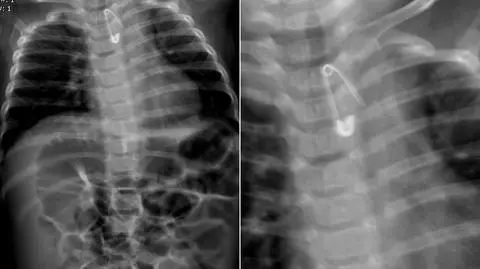

Tę historię obszernie opisywaliśmy na tvn24.pl w lutym. Sześciomiesięczny Kuba połknął agrafkę we wrześniu 2018 roku. Przerażeni rodzice zawieźli dziecko do najbliższej placówki, czyli na SOR w Krotoszynie. Dyżurująca lekarka zleciła szereg badań. RTG potwierdziło: metalowy przedmiot tkwi w przełyku. W placówce nie było odpowiedniego sprzętu, by usunąć agrafkę, dlatego dziecko skierowano do szpitala specjalistycznego w Ostrowie Wielkopolskim.